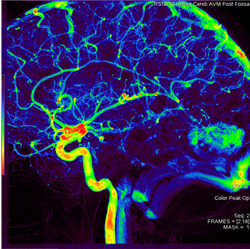

AngioViz uses peak time and density with color as time, and peak density as brightness to show contrast flow timing and magnitud

In one image, AngioViz can show peak pixel density value over an image series. This can indicate relative contrast density and d

AngioViz can show the time that each pixel reaches peak density on a color coded time scale. This helps indicate contrast flow t

A New Visualization of Vascular Flow

AngioViz provides a new visualization of the vascular flow seen in DSA imaging, utilizing a technique called parametric imaging. AngioViz looks at each pixel in the image series and determines two things — the peak value of opacification caused by the contrast, and the time it takes for that pixel to reach peak opacification. These two parameters can be displayed as separate images or combined into a single color-coded image that represents parameters of vascular flow. This enables doctors to perceive parameters of flow quickly to support decision-making. In addition, AngioViz allows easy comparison of parametric images from different DSA acquisitions, such as pre- and post-treatment images. This can help physicians understand the impact on flow dynamics of various interventional treatments.